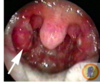

What is labelled A Chlamdyia infection Endometriosis Fibroids Gonorrhea infection Polycysitc ovary syndrome